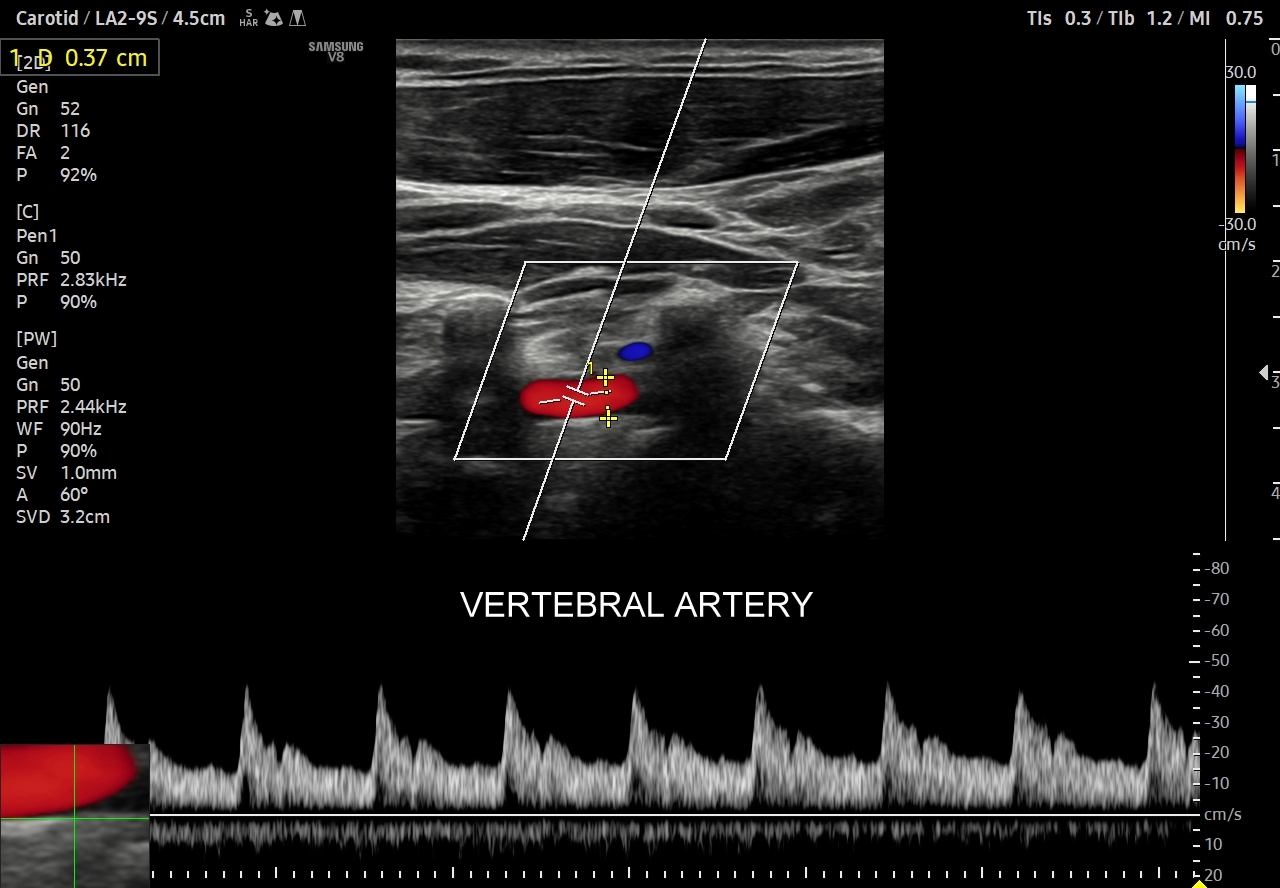

- Profile o niskiej pulsacyjności (ang. low-pulsatility) cechują się szerokim pikiem skurczowym, praktycznie ciągłym przepływem przez całą fazę rozkurczową i monofazowością. Profile tego typu występują w tętnicach unaczyniających bezpośrednio mózg, siatkówkę, tarczycę, wątrobę, śledzionę, nerki.

Oprócz przepływów typowo niskooporowych oraz typowo wysokooporowych istnieją profile przepływów o pośredniej charakterystyce, np. w tętnicy szyjnej wspólnej. Z kolei w przypadku tętnic kręgowych w zależności od ich szerokości fizjologicznym jest obserwowanie zarówno profilu niskooporowego w przypadku dużej średnicy, jak i wysokooporowego w przypadku małej średnicy.